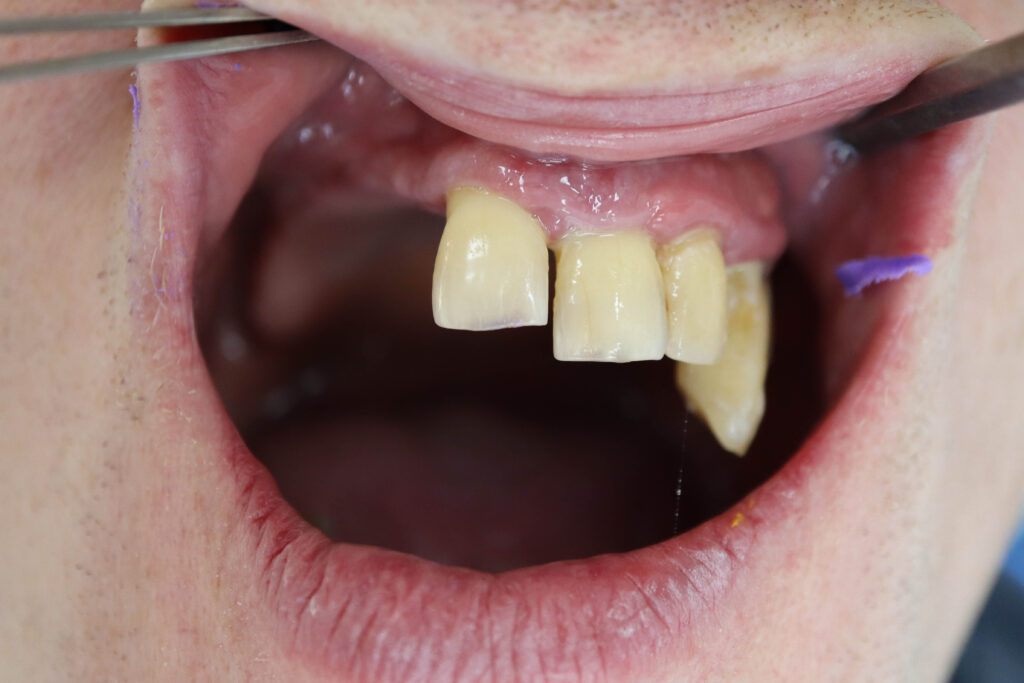

Результат

Результат имплантации